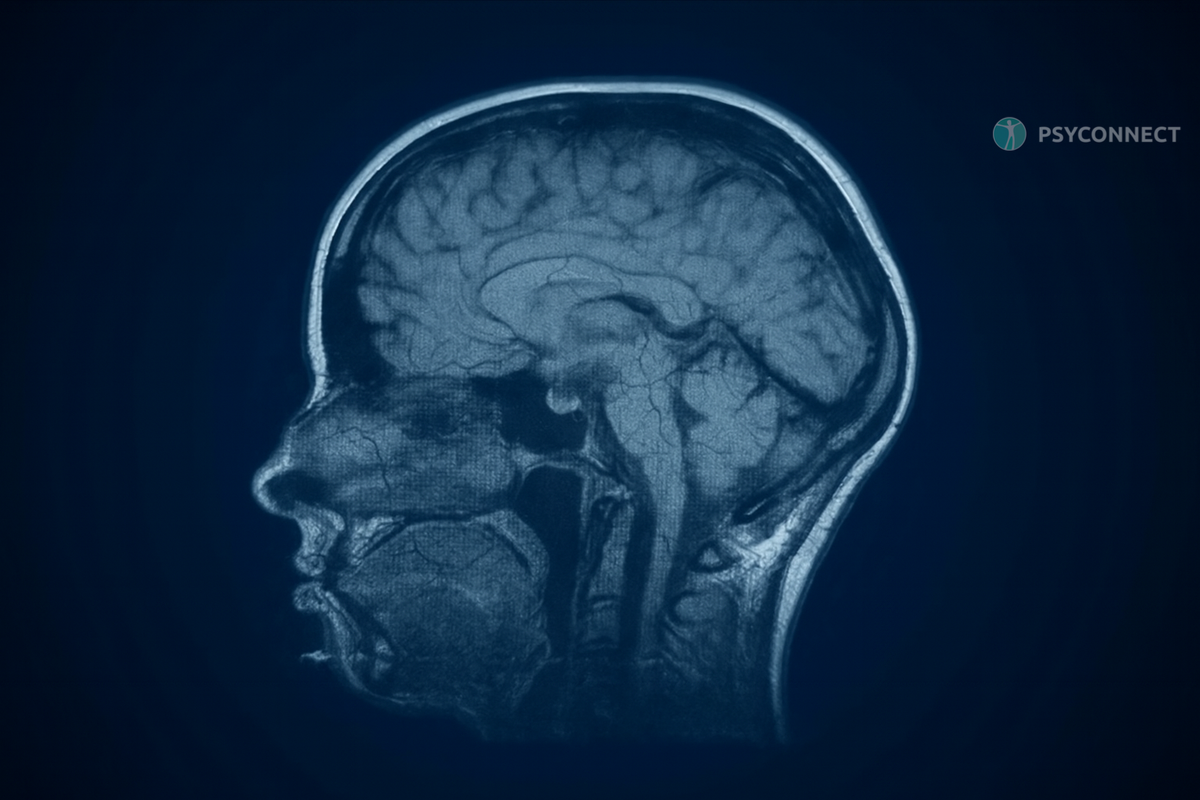

Первое. Меняется структура мозга. Физически.

Обычно, говоря об эмоциональном насилии, вспоминают боль, тревогу, слёзы. Но мало кто задумывается, что оно меняет саму ткань мозга. Хронический стресс заливает его гормонами тревоги, прежде всего кортизолом. Из-за этого уменьшается гиппокамп - область, отвечающая за память и обучение. Становится трудно сосредоточиться, усваивать новое, запоминать обычные бытовые вещи. День за днём будто стирается.

Одновременно страдает префронтальная кора - та часть мозга, которая помогает принимать решения и контролировать импульсы. Если ты ловил себя на ощущении, что застрял в круге плохих решений, будто не можешь вырваться из разрушительных сценариев, это не слабость характера. Это следствие насилия. Мозг перестраивается так, чтобы ты жил только текущей болью, не видя будущего.

Второе. Гиперактивная миндалина. Жизнь в постоянном страхе.

Ты постоянно напряжён, даже когда объективно ничего не угрожает? Это работает миндалина - центр страха. Именно она запускает реакцию "бей или беги".

При эмоциональном насилии миндалина становится чрезмерно активной. Ты чувствуешь тревогу, страх, ожидание беды без реальной причины. Это как фоновый шум, который не выключается ни днём, ни ночью. Ты не можешь расслабиться. Не можешь почувствовать безопасность.

Ты начинаешь резко реагировать на мелочи, ждать худшего, быть всегда настороже. И это не просто состояние ума. Это физическое изменение мозга, которое изматывает и опустошает.